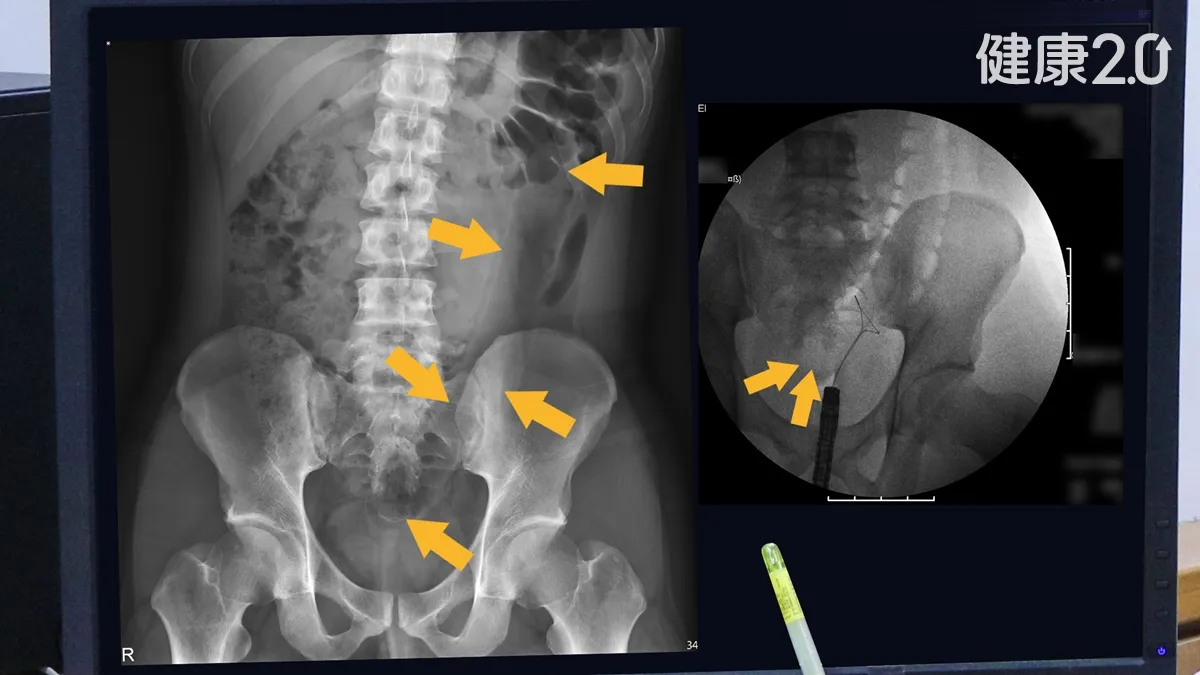

男尋刺激險送命!35公分長情趣按摩棒 塞肛門拿不出

...醫師觸診時已經摸不到按摩棒,照X光檢查才確認按摩棒已經深入到乙狀結腸底部,距離肛門口已有20公分遠,頂端已經到達降結腸。看更多:...